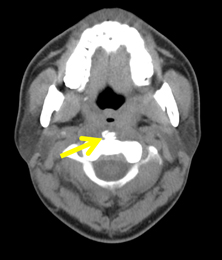

Crowned dens syndrome と石灰沈着性頸長筋腱炎。

crowned dens症候群の画像診断!まるで王冠。